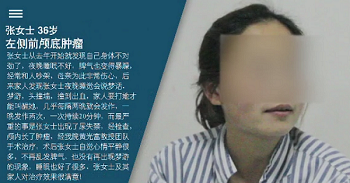

患者辗转多院后来到我院,经门诊医生进行流行病史调查无新型冠状病毒肺炎地区旅游集居住史,无新型冠状病毒肺炎密切接触史,无发热、乏力、咳嗽及腹泻症状,门诊血常规、CRP、 胸部cT检查,排除新冠状病毒肺炎,门诊以“左侧前颅底肿瘤”收入我科。之后在我院进行了肿瘤切除手术。

患者因“月经不调、性格情绪改变、睡眠差,睡眠中抽搐伴梦游”于2020-04-20 入我院。

1、患者青年女性,起病缓,病程长。以月经不调、性格情绪改变、睡眠差为主要临床表现。

2、现病史:3年多前,患者生育二胎后无明显诱因出现睡眠差,夜间入睡慢,入睡后易醒,多梦等症状。且近3年来性格变化大,情绪激动,易怒,月经紊乱,自诉烦渴,饮水量不多,小便量多,生育后2年多无月经,近半年经期紊乱,经量少,经期及间隔周期均不规律。

患者半年前于“贵阳中医一附院”就诊,口服安神补脑液等药物治疗,症状无明显好转。2个多月前,患者家属发现患者夜间睡眠中突发四肢强直、双眼向上凝视、牙关紧闭,伴有舌咬伤,每次发作时间10-20分钟,发作后患者常有漫无目的四处游走,偶有尿失禁,上诉症状基本隔天发作, 患者平素无明显头晕头痛、视物旋转,无恶心、呕吐,无畏光、畏声,无明显加重缓解因素。

患者1月前于贵黔国际总医院,行头颅MRI示:鞍上占位,脑电图:异常脑电图(左侧颞中央区局灶性改变) 。医院建议手术治疗,遂就诊于贵州医科大学附属医院,行头颅CT:鞍上池区域占位,考虑畸胎瘤可能,建议转院手术治疗。